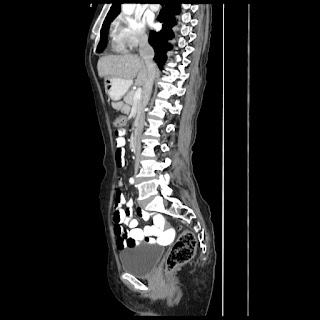

A 65 years old woman suffering with pain in left hypochondrium region since 2 month's

C/O:- Pain in left side hypochondrium region since 2 month.

H/O: - Cow struck by head & injury to abdomen 6 month back.